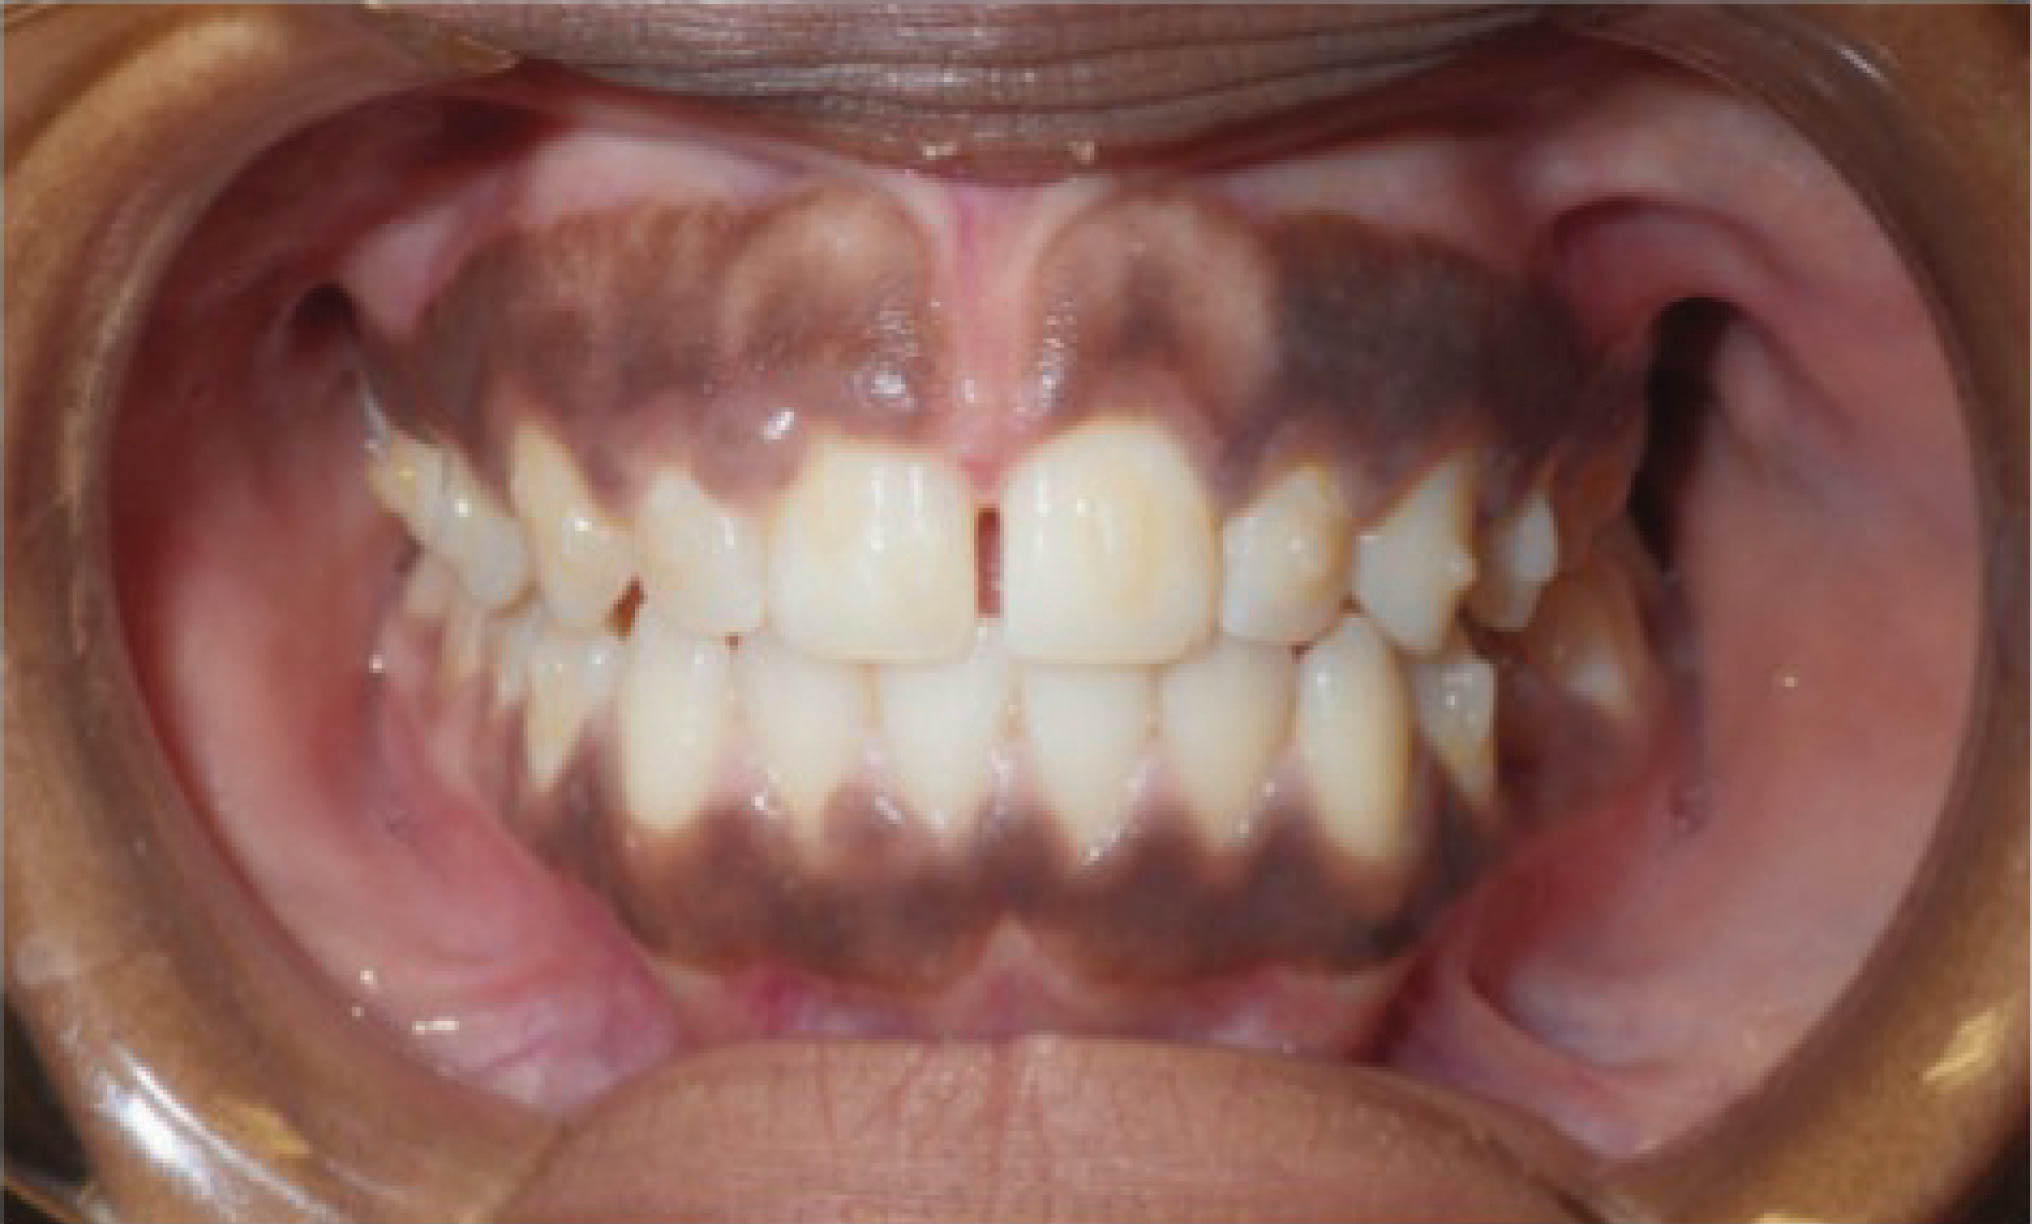

در بیمارانی که انسیزورهای بیرون زده با فضای بین دندانی دارند و آنها را به عقب میبریم احتمال تیپ شدن دندانها حتماً وجود دارد (شکل 41-6 و 42-6).

در بیمار شکل 43-6 و 44-6، انسیزورهای بالا و پایین با تیپ کردن لینگوالی آنها به عقب کشیده شدند تا هم فضا بسته بشود و هم دندانها عمودتر قرار بگیرند.

شکل 41-6

شکل 42-6

شکل 43-6

شکل 44-6